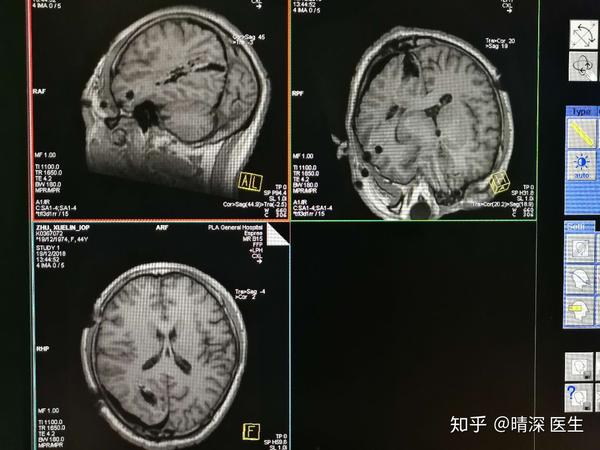

Mri Mrs Mra是什么检查 医学mrs是什么检查 桃丽网

一文读懂mrs评分 神经介入临床评分小工具 系列介绍